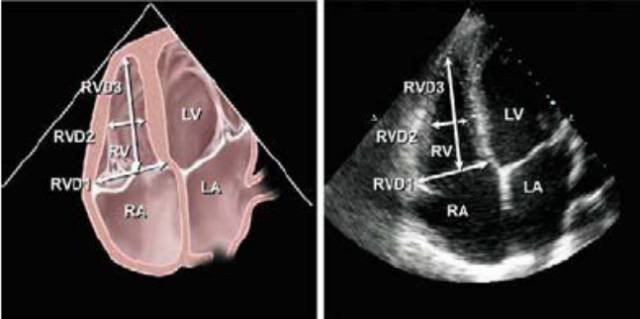

4、右心室大小的评估

由于右心室的几何构型复杂、定量评估困难,目前临床上多采用右心室的面积或内径与左心室对比来作出定性评价。

5、右心室舒张末期面积

右心室的大小(与左心室二维面积比较)

6、右心室舒张末期内径

右室基底段舒张末期横径小于等于42mm;

右室中段舒张末期横径小于等于35mm;

右室舒张末期长径小于等于86mm。